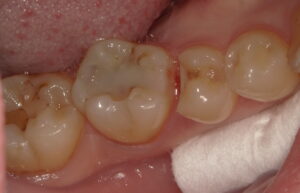

今回の患者さんは歯ぎしりの自覚があり、虫歯のなりにくさや詰め物の強度を考えてゴールドを選択されました。

装着前